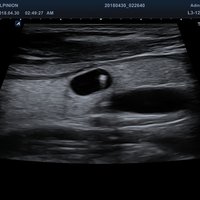

• EV3-10T (3-10 MHz) für Ultraschalluntersuchungen in Bereichen Geburtshilfe, Gynäkologie, fetales Echo, Urologie

• EC3-10T (3-10 MHz) für Ultraschalluntersuchungen in Bereichen Geburtshilfe, Gynäkologie, fetales Echo, Urologie